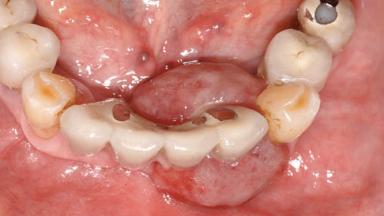

Case Type Extended Space

Jaw Mandible

Area Anterior|Posterior

# of Teeth 10

# of Implants 5

Type of Implants One-Piece